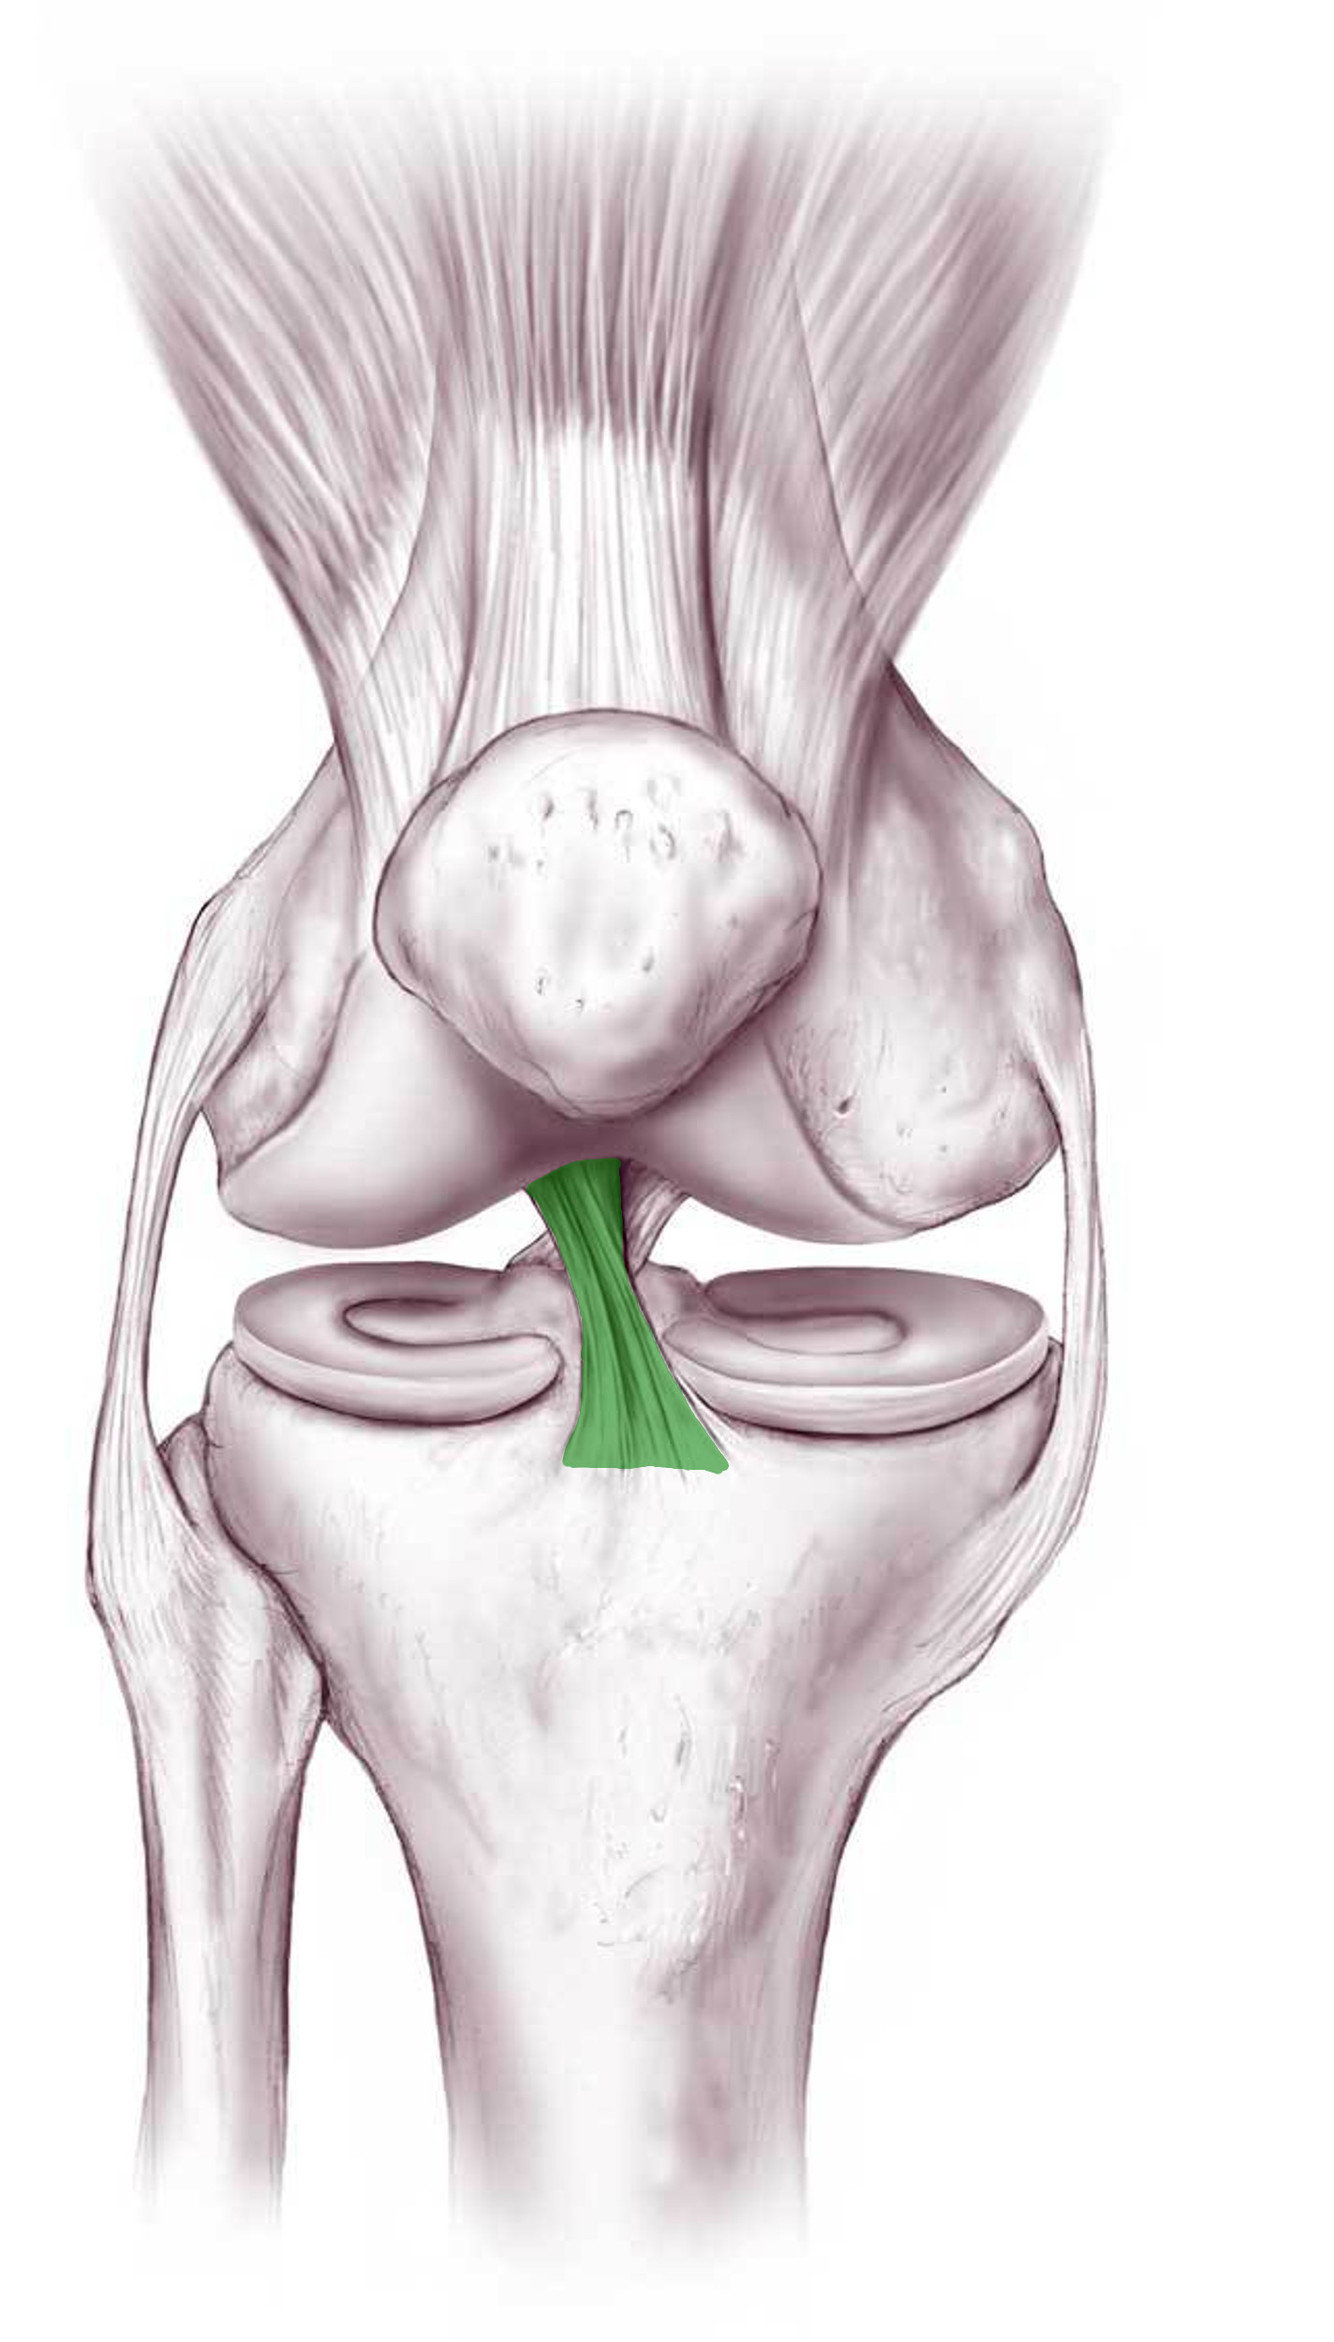

What is this structure?

Anterior cruciate ligament of the knee

What is this structure?

Posterior cruciate ligament of the knee

What is the function of this structure?

Anterior cruciate ligament of the knee

Stops anterior dislocation of knee

What is the function of this structure?

Posterior cruciate ligament of the knee

Prevents femur from sliding posteriorly on tibia